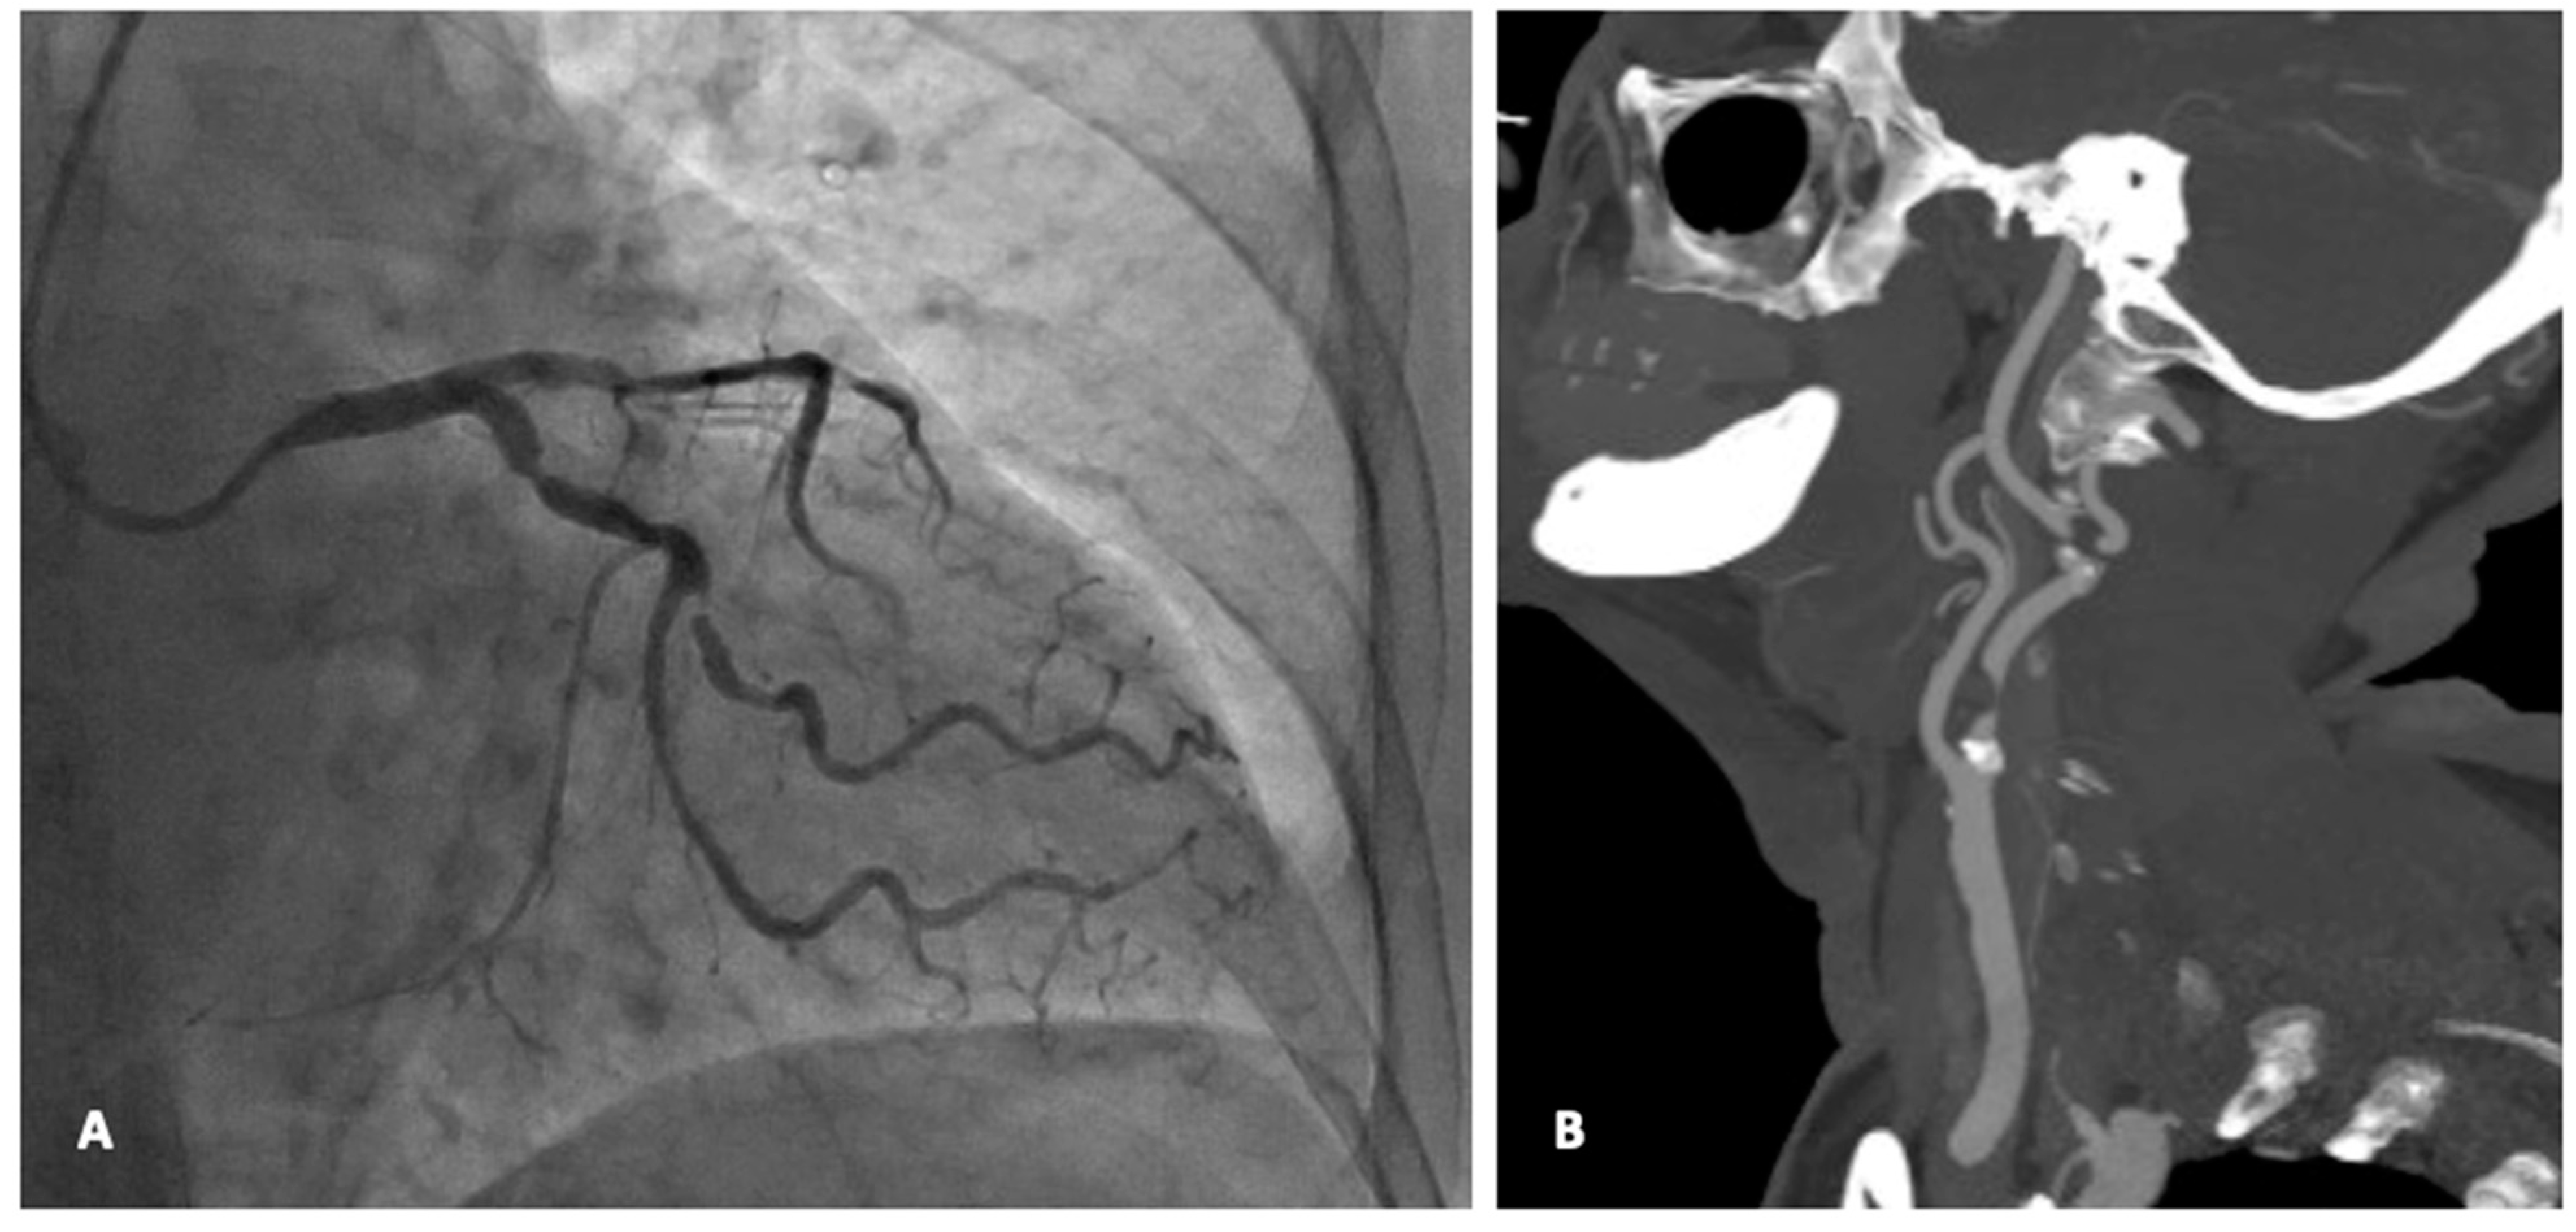

- Hybrid approach: synchronous CAS + CABG

- Hybrid approach: staged CAS + CABG

- Dzierwa, K.; Pieniazek, P.; Musialek, P.; Piatek, J.; Tekieli, L.; Podolec, P.; Drwila, R.; Hlawaty, M.; Trystula, M.; Motyl, R.; et al. Treatment strategies in severe symptomatic carotid and coronary artery disease. Med. Sci. Monit. 2011, 17, RA191–RA197. [Google Scholar] [CrossRef] [PubMed]